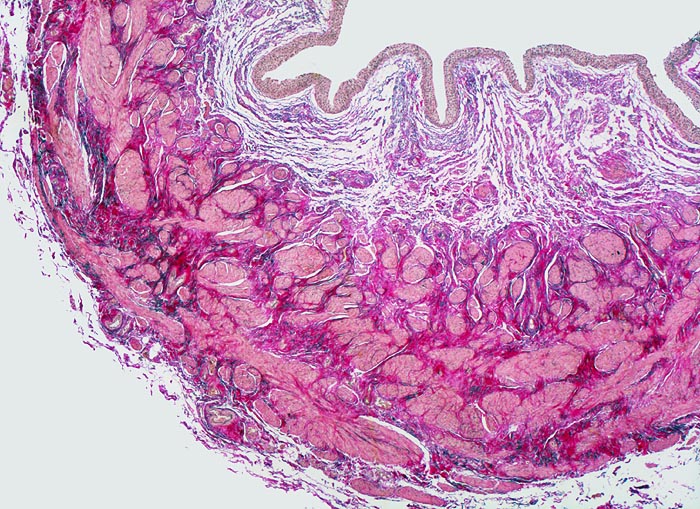

• Transurethrale Resektate von Harnblasenschleimhaut mit papillärem Tumor.

• Entnahmebedingte Kauterartefakte (dünn ausgezogene Zellen und Chromatinschlieren, ausgefranste Abtragungsränder).

• Das neoplastische Urothel bildet fingerförmige, teils miteinander verschmelzende Papillen mit schmalen fibrovaskulären Stromastielen.

• Das neoplastische Urothel ist verbreitert (meist mehr als 7 Zellagen).

• Scharfe Grenze zwischen Epithel und subepithelialem Stroma (keine Invasion).

• Mässiggradige Dysplasie des neoplastischen Urothels (G2, low grade): Tumorzellen mit vergrösserten, leicht pleomorphen Zellkernen. Zahlreiche Apoptosen. Herdförmiger Polaritätsverlust (fehlende Ausrichtung der Zellen in der Längsachse).

• Auf diesem Schnittpräparat sind kein tumorfernes Urothel und keine Anteile der Harnblasenwandmuskulatur enthalten.